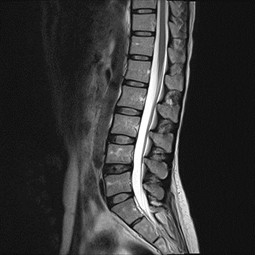

Degenerative Lumbalskoliose Wenn sich der bereits beschriebene Verschleiß in mehreren Wirbelelementen findet, kann es zu einer Verkrümmung der Wirbelsäule zur Seite hin (sog ‚Skoliose‘) kommen Normalerweise tritt eine Skoliose im Alter zwischen 10 und 12 auf. Die weitaus häufigsten degenerativen Beschwerden der Wirbelsäule finden sich im Lendenwirbelsäule (LWS) Bandscheibenvorfälle Bei Bandscheibenvorfällen (Abb 4a und 4b, MRT bei Bandscheibenvorfall LWK 3/4 rechts) wird zumeist über einen dorsalen Zugang eine mikrochirurgische Operation vorgenommen (Mikrodiscektomie). Im Laufe des Lebens kann es anlagebedingt, sowie durch allgemeinen Verschleiß zu Veränderungen der anatomischen Charakterzüge kommen, so dass die funktionellen Eigenschaften der Wirbelsäule beeinträchtigt werden Diese Veränderungen werden als degenerative Veränderungen bezeichnet.

Bandscheibenvorfall Lws Innsbruck Dr Unterhofer